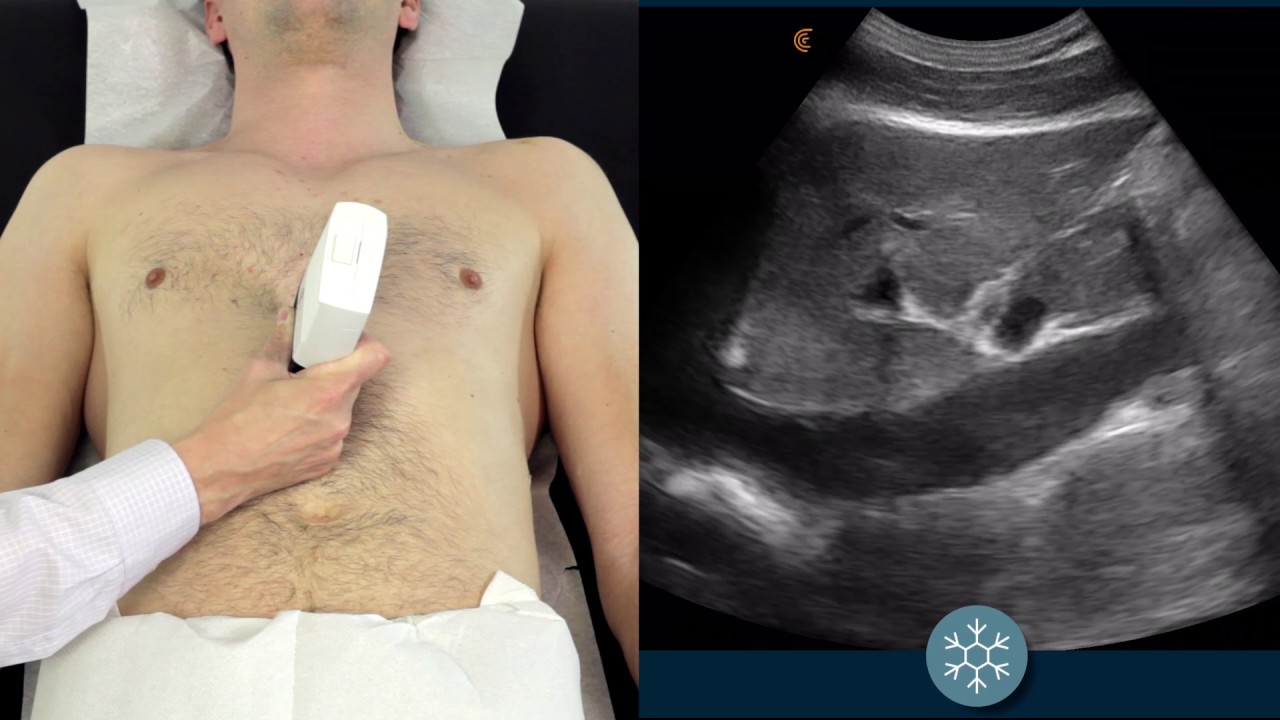

Vediamo IVC Ultrasound | How to assess the IVC for volume status using ultrasound | Clarius Ultrasound aggiornato